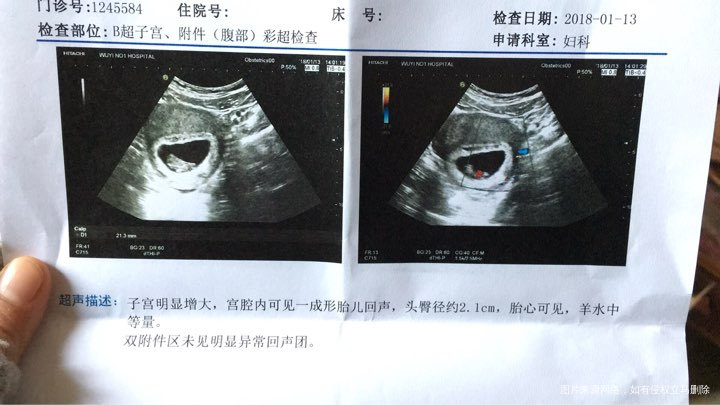

下面是本月13号B超单